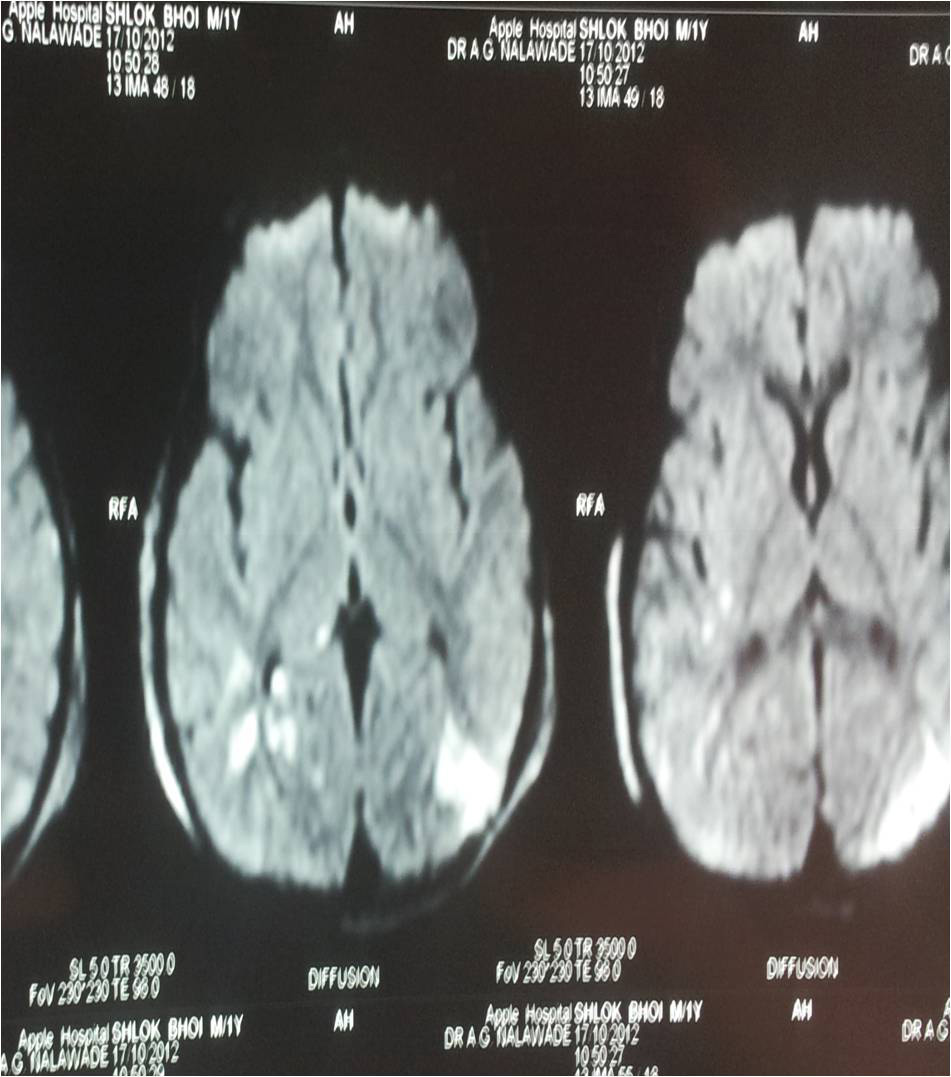

MRI of Dai

• MRI of Dai